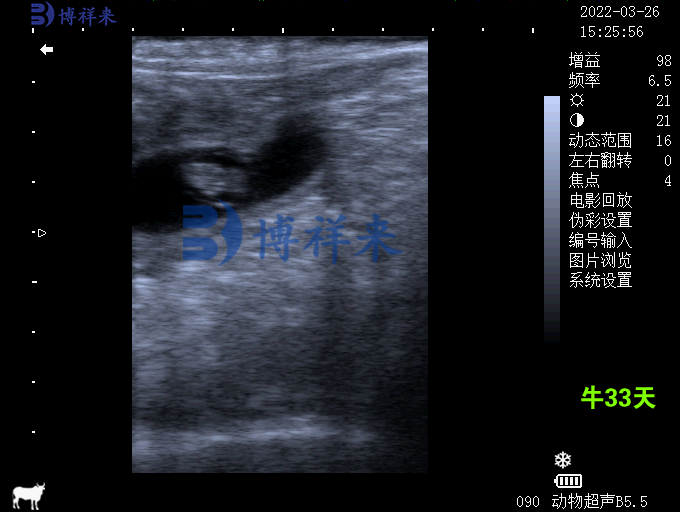

母牛妊娠33天超声图像